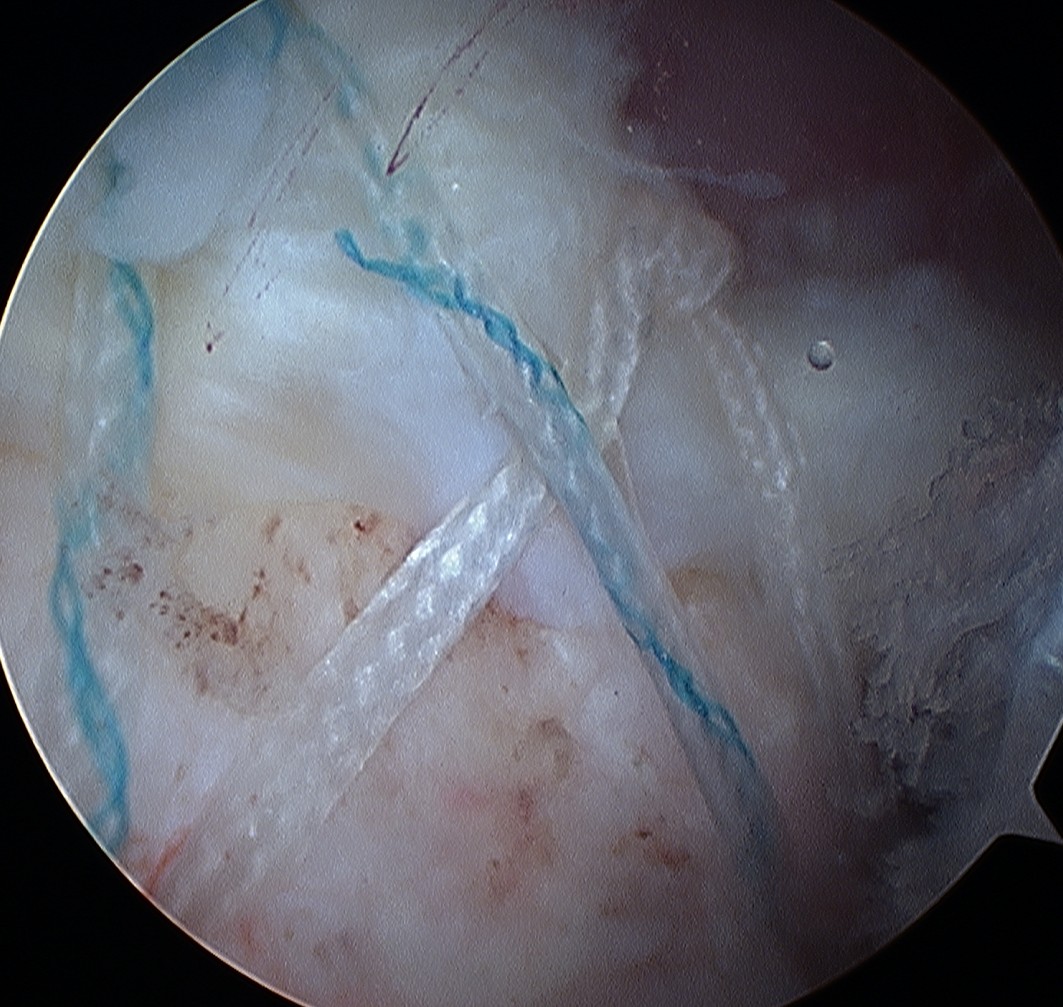

D. Transosseous equivalent / suture bridge

Technique

- biomechanically replicate tradional open transosseous

- sutures crossed as below in double row

- aiming to increase contact between cuff and footprint

Double row

- either pass second lateral row of anchors or

- use foot print anchors, retrieve previous sutures

- can make suture bridge configuration

- check repair via lateral portal